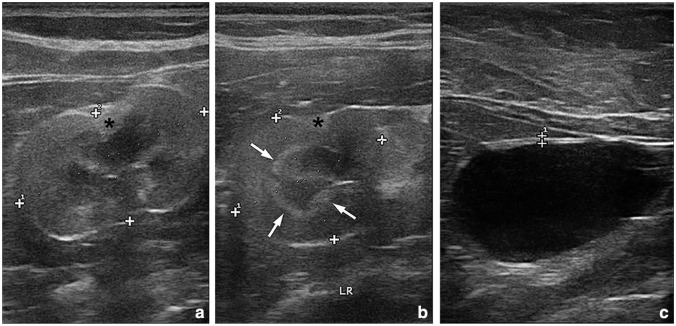

Case summary: A 13-year-old male castrated domestic shorthair cat presented with a 2-month history of progressive lameness, poor appetite and constipation. Physical examination revealed palpable lesions in muscles of several extremities. Ultrasound examination confirmed the presence of round lesions with a hypo- or anechoic centre within the muscles. These lesions were characterised by an anechoic, occasionally trabeculated, central area surrounded by a hyperechoic band with heterogeneous echotexture. In total, seven lesions affecting six appendicular muscles were detected in different evolution stages, as suggested by their sizes and ultrasonographic features. Fine-needle aspiration of the muscle lesions revealed nests and isolated pleomorphic large neoplastic cells consistent with a carcinoma (vs sarcoma) and one mass was surgically removed. The histological and immunohistochemical studies confirmed a diagnosis of metastatic urothelial carcinoma. Although this neoplasia typically originates from the urothelium of the urinary bladder or renal pelvis, the primary tumour could not be detected in repeated abdominal ultrasound examinations. The cat was euthanased and further evaluations were declined by the author.

Relevance and novel information: Urothelial carcinoma is a rare and highly aggressive neoplasia in the cat. While metastasis to regional lymph nodes and lungs are common in cats and dogs, to the authors' knowledge, there have been no reports of metastasis to multiple appendicular muscles in cats. This clinical presentation should be considered in the differential diagnoses of multiple nodular or cystic lesions affecting long muscles in cats.